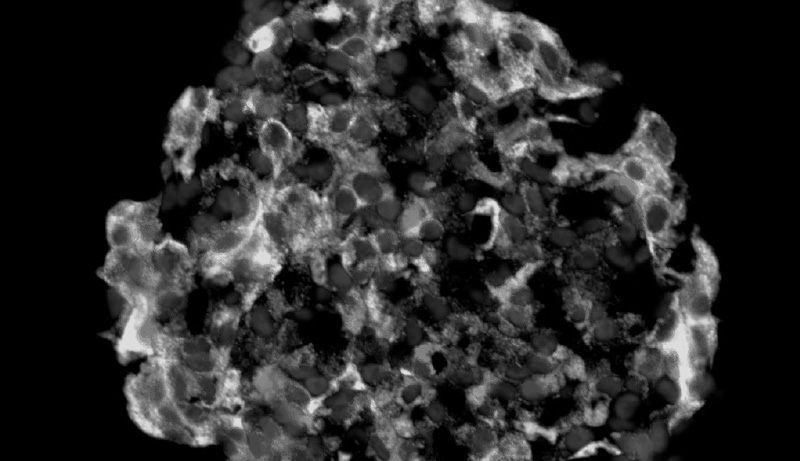

Pancreatic beta cells produce, store, and release insulin in order to regulate blood glucose levels. Beta cells (sometimes written as β-cells) are located in the pancreatic endocrine structures called the islets of Langerhans.

Image source: Stem cell-derived beta cells made by the Douglas Melton lab and provided for educational purposes only.